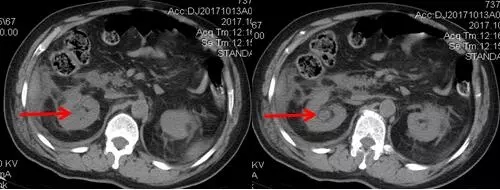

術(shù)后CT,箭頭所指為腎結(jié)石被徹底清除

三日后,曾奶奶病情逐漸穩(wěn)定,各項感染指標(biāo)逐漸恢復(fù)正常,復(fù)查CT顯示腎結(jié)石已經(jīng)被完全清除,現(xiàn)已康復(fù)出院。就此,困擾曾奶奶多年,反復(fù)感染差點致命的腎結(jié)石頑疾被徹底治愈。曾奶奶全家人對于愛康醫(yī)院泌尿外科專家高超的碎石取石手術(shù)技藝更是贊許有加,對泌尿外科團(tuán)隊的工作給予衷心感謝和高度評價。